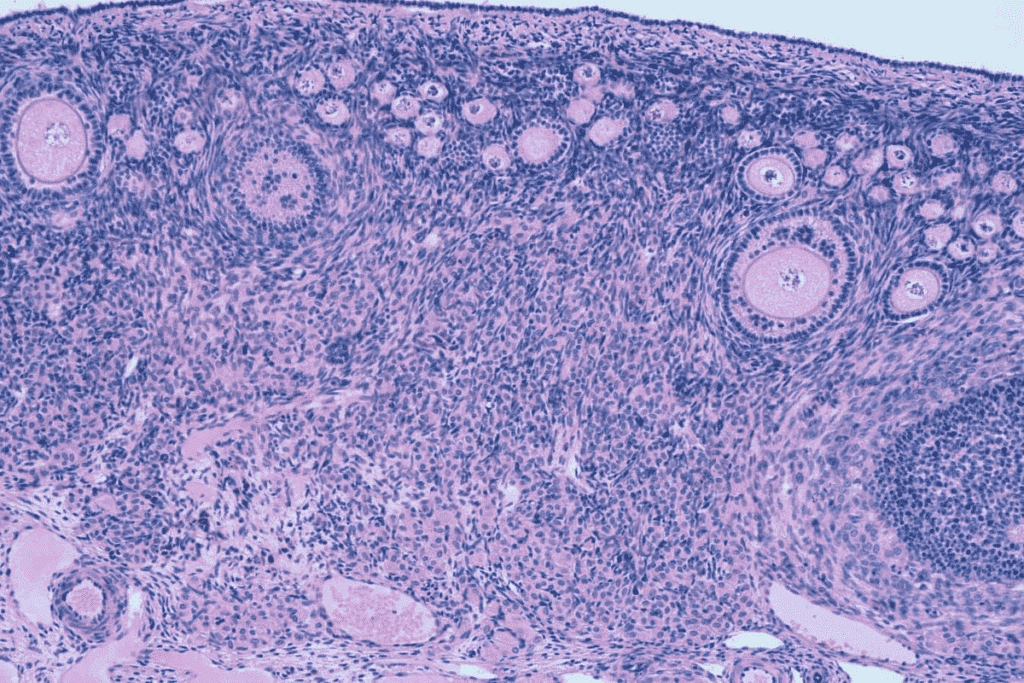

Understanding the IVF Follicle Development Process

The IVF follicle development process is a delicate balance. It combines natural growth with medical stimulation. This balance is key for patients to understand.

We watch follicle growth closely with ultrasound scans and hormone tests. This helps us find the best time for egg retrieval. The size of the dominant follicle is the main factor.